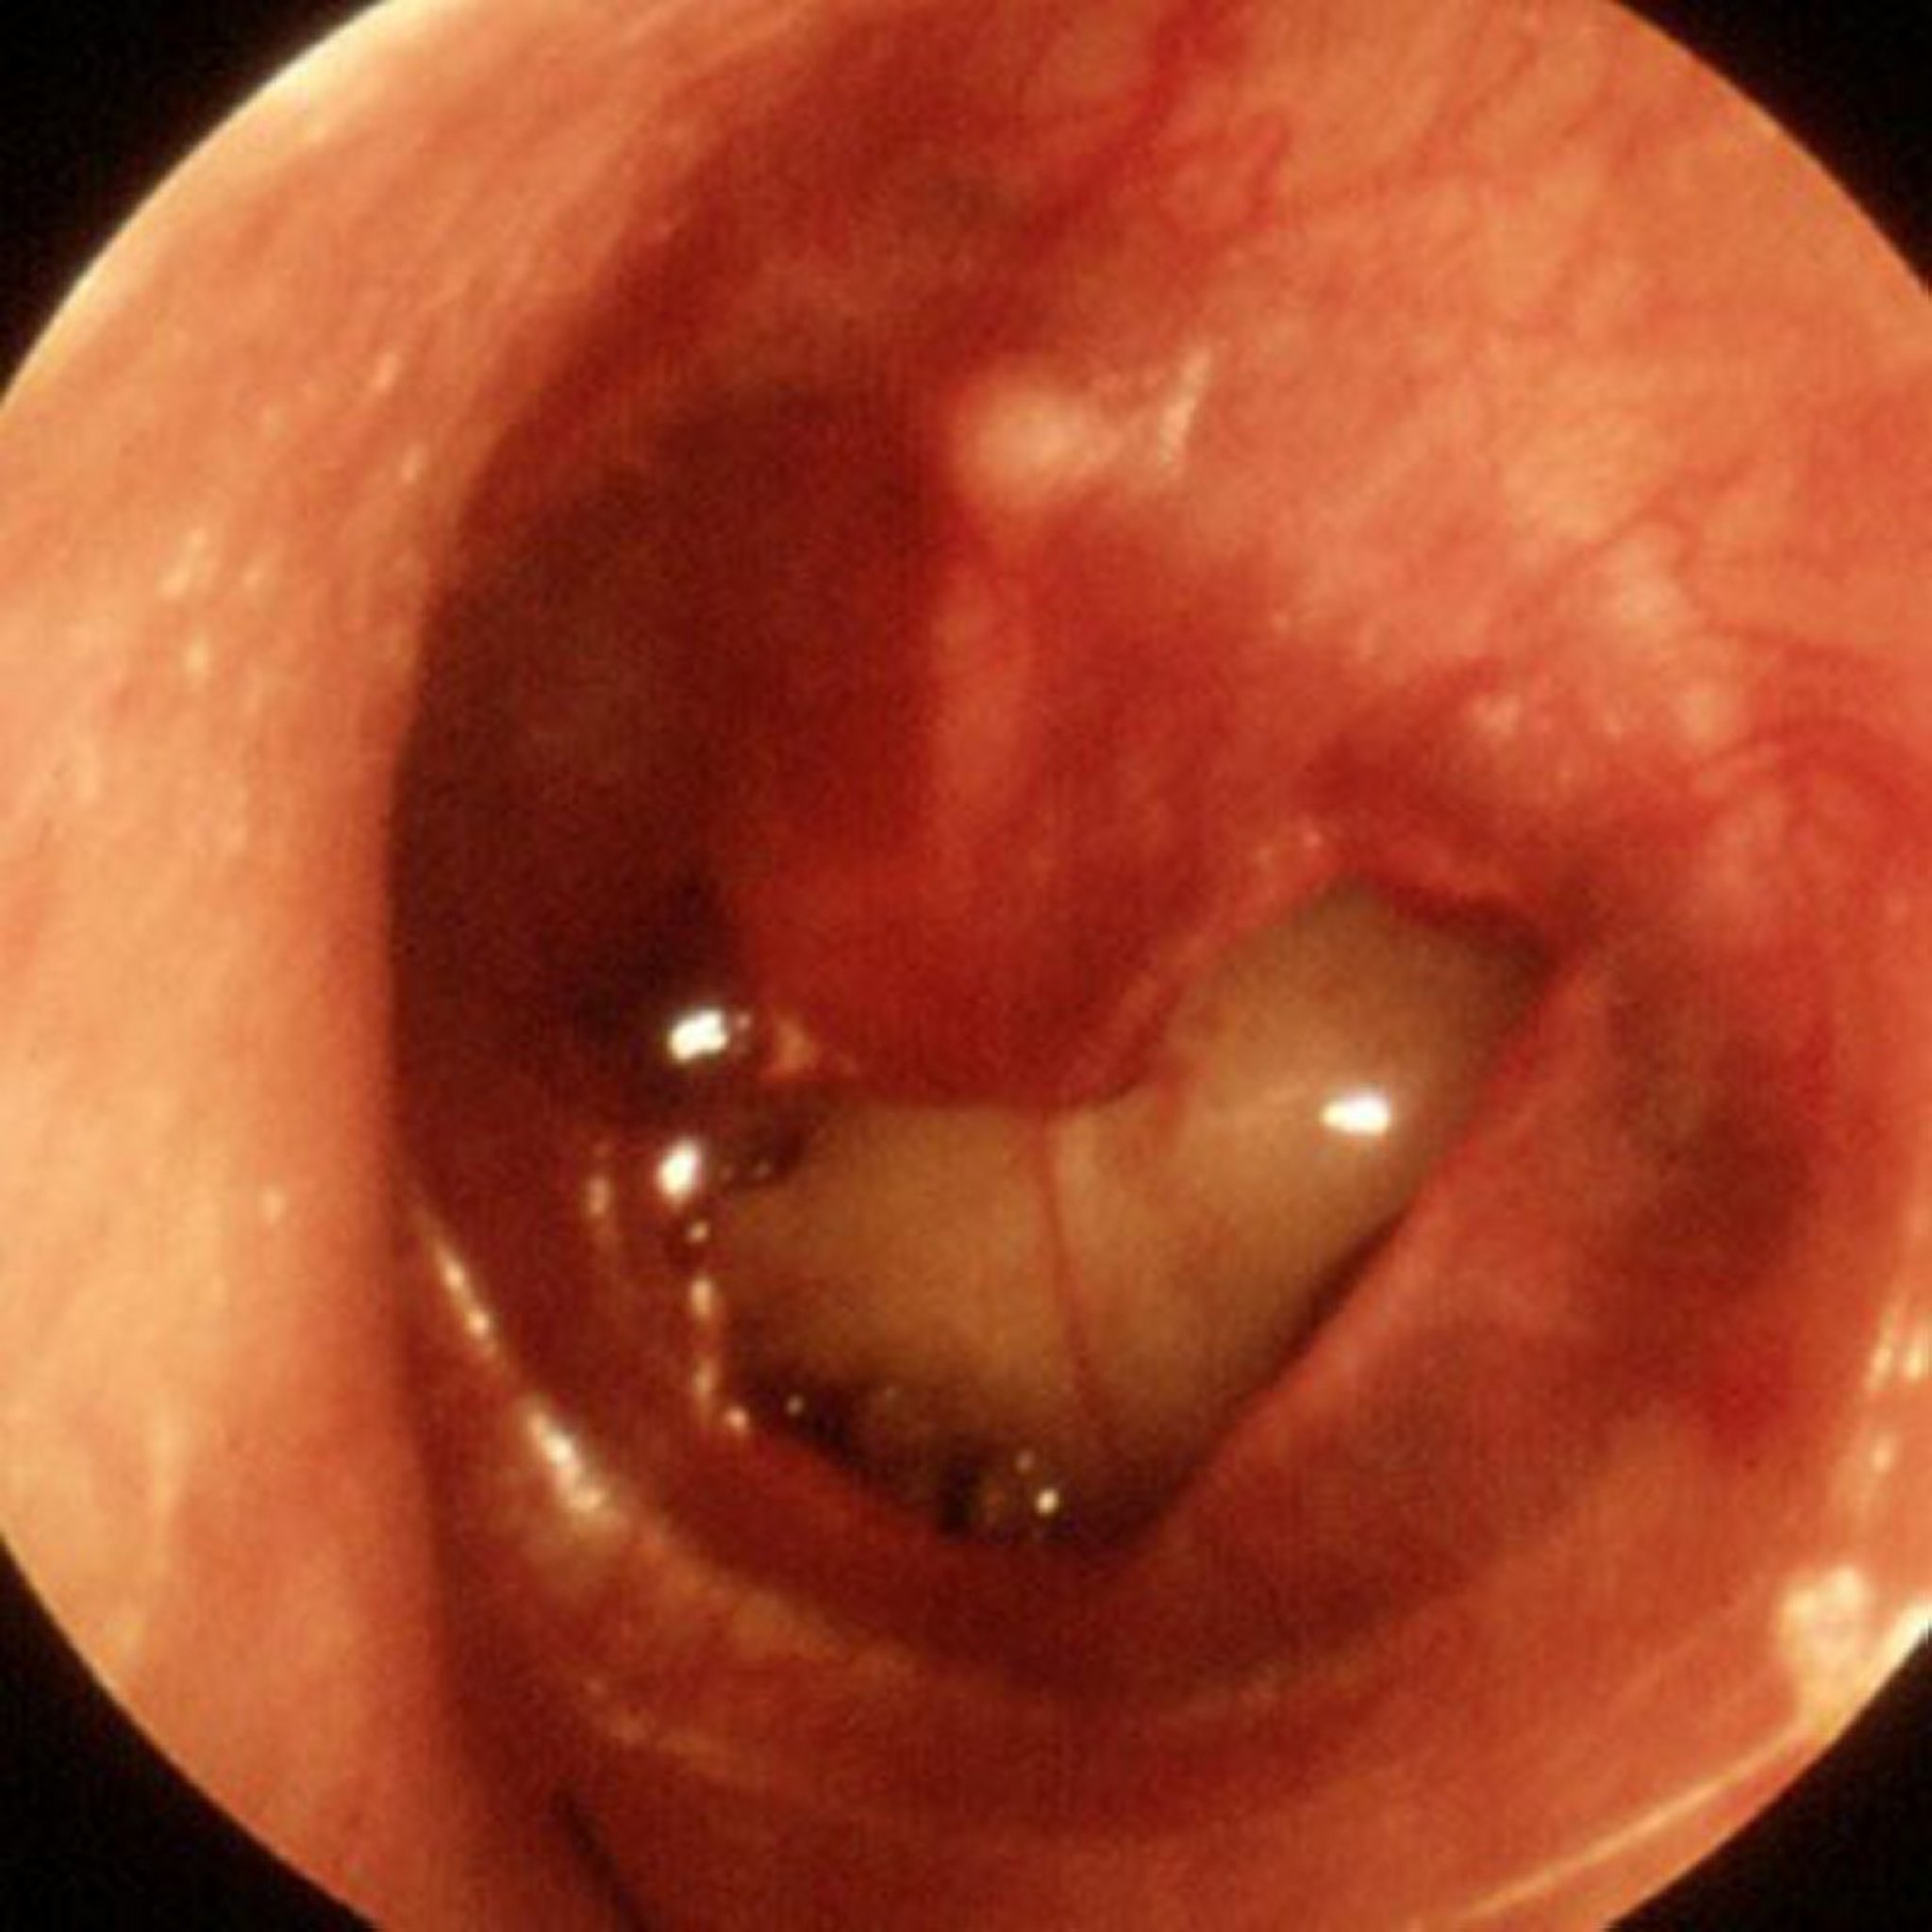

Traumatic Perforation of Tympanic Membrane

A large traumatic perforation is seen in this image.

Image provided by Piet van Hasselt, MD.